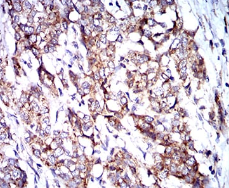

| AC1297 | BNIP3 Mouse Monoclonal antibody[6A5F7] | 100ug | $367 | 10days |

| AC1297 | BNIP3 Mouse Monoclonal antibody[6A5F7] | 200ug | $660.6 | 10days |